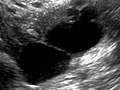

Pelvic Ultrasound

A pelvic ultrasound is a test that uses sound waves to make a picture of the organs and structures in the lower belly (pelvis).

Organs and structures that are solid and uniform (such as the uterus, ovaries, or prostate gland) or that are fluid-filled (such as the bladder) show up clearly on a pelvic ultrasound. Bones may block other organs from being seen. Air-filled organs, such as the intestines, can make the image less clear.

In all of these ultrasounds, the transducer sends the reflected sound waves to a computer, which makes them into a picture that is shown on a video screen. Ultrasound pictures or videos may be saved as a permanent record.